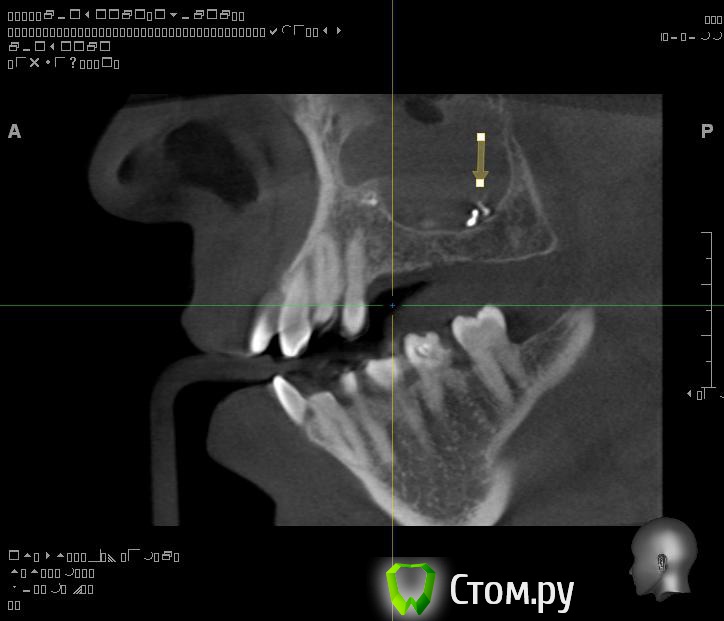

Евений Опубликовано 22 ноября, 2013 Поделиться Опубликовано 22 ноября, 2013 (изменено) Здравствуйте!В 2011 году делал КТ. Заполнена тотально правая пазуха, у медиальной стенки инородное тело овоидной формы, в центре которого объект металлической плотности, мелкие объекты на нижней стенке пазухи. Полипы у носового хода.После этого была радикальная гайморотомия на правой пазухе. Обнаружили застарелый хронический процесс, творожистые массы, поставили холеастому. Гистология операционного материала показала наличие грибка.По своей инициативе сделал 3d-томографию на picasso trio.Рентгенолог сказал про уровень в пазухе и инородное тело.КТ делал во время простуды, был насморк.Сходил на консультацию к профессору, который меня оперировал. Внимательно осмотрев носовую полость он ничего не нашел. Про КТ сказал, что это могут быть корни зубов. Пломбировочный материал отрицает, как и перед операцией. На данный момент - простуда, и оперированную пазуху закладывало больше чем здоровую. Выделения прозрачные, потом желтые и оранжевые.. Из минусов, как и раньше стекает слизь по задней стенке. Вопрос такого плана: Что за загогулины в правой оперированной пазухе? Целесообразно ли делать микрогайморотомию после радикальной, или если будут делать то опять радикальную?Спрашиваю потому, что уже не знаю к кому обращаться у нас в Архангельске. Вроде, операция радикальная была под контролем эндоскопа, уж должны были всё проверить и достать. Делал операцию академик, светило медицины в области хирургической стоматологии и онкологии.И еще - а стоит ли вообще делать вторую операцию? Возможно вред от вмешательства и наркоза перетянет пользу операции. Спасибо!ССЫЛКА НА РЕЗУЛЬТАТЫ ПИКАССО ТРИО http://dfiles.ru/files/qc62dn476 Изменено 22 ноября, 2013 пользователем Евений Ссылка на комментарий

АнтонТЛТ Опубликовано 22 ноября, 2013 Поделиться Опубликовано 22 ноября, 2013 Найдите хорошего ЛОРа, который нормально уберет остатки пломбировочного материала 2 Ссылка на комментарий